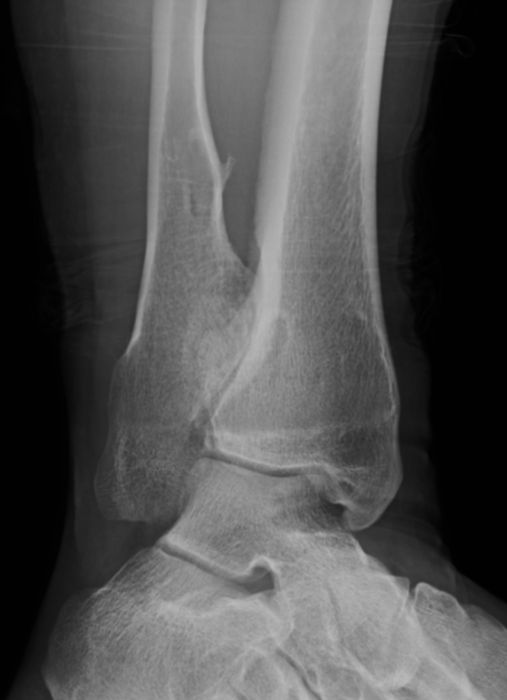

Ankle

- valgus

- fibular shortening with valgus distal tibia

- wedge-shaped distal tibial epiphysis

- leads to valgus talar tilt in abnormal mortise

Ankle mult OC 1Ankle mult OC 2

Incidence

Zhang et al J Child Orthop 2021

- 61 children, mean age of 10

- 50% had ankle valgus

- correlates with osteochondromas lateral tibia / medial fibula